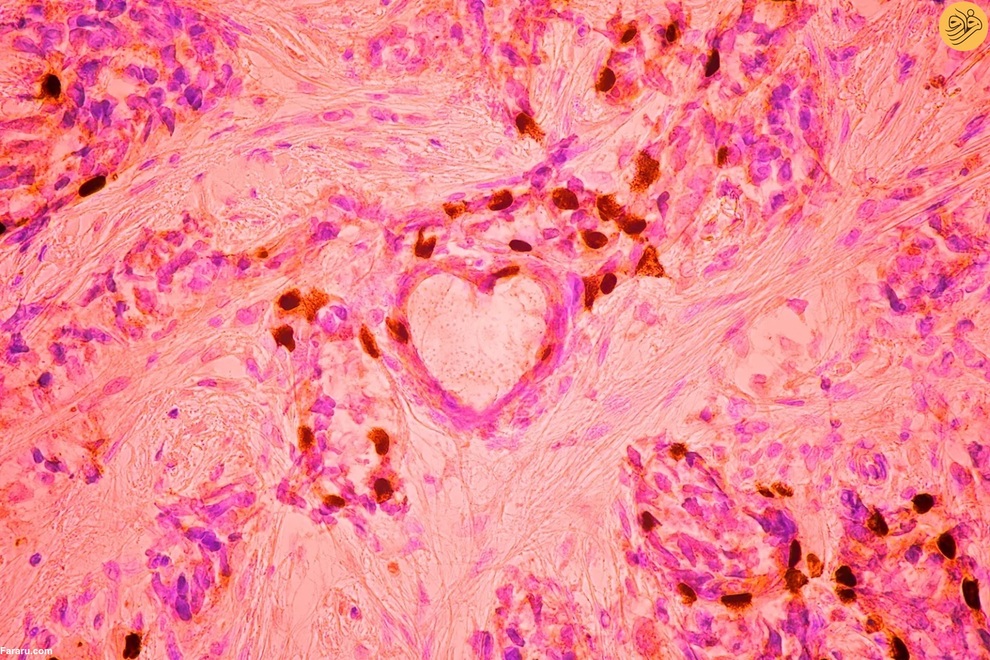

عروق خونی و لنفاوی در پوست گوش موش بالغ. عکس از ساتو پااوونسالو و دکتر سینم کارامان